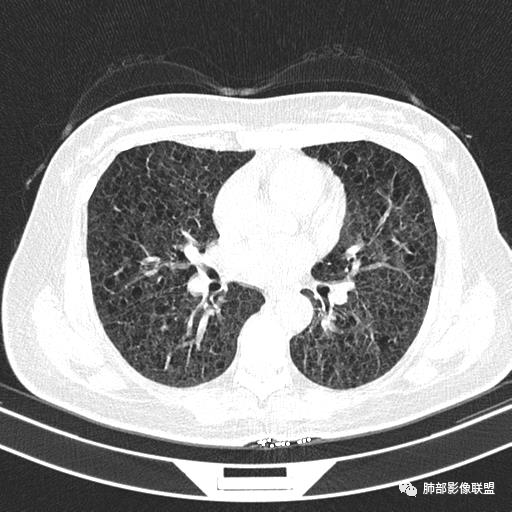

CT平扫示双肺弥漫分布大小不等囊状薄壁透光区,无内、中、外带分布差异,间质稍示增厚。拟LAM

中年女性育龄期妇女,咳嗽气喘,无吸烟史,有苯吸入史。影像:双肺弥漫均匀小囊腔,无明显分布优势,囊腔形态欠规则,壁薄,部分囊腔边缘血管征,伴双肺弥漫磨玻璃影,无结节,考虑lam,鉴别苯中毒肺损伤,囊腔多有分布优势,小叶中心分布为主,形态规整等

女,46,活动性气喘1年。苯吸入史半年。胸部CT:两肺弥漫囊腔,上至肺尖,下至肋膈角,形态类似小囊腔。考虑:LAM,鉴别LIP,BHD,PLCH等。

双肺弥漫大小不一薄壁含气囊腔,囊间肺组织正常,正常肺背景,肺尖肺底受累;青年女性,气喘,支持LAM

CT表现:双肺弥漫大小不等的薄壁囊腔,囊壁<2mm,外形规则,血管影多位于囊腔周围,囊腔之间肺组织正常,随着疾病进展到晚期,囊腔变大、增多,不可胜数,囊腔可融合成较大的囊,与肺气肿相似,形成间质性肺纤维化。部分病例可出现结节影。

临床诊断BHD综合征需要满足一个主要或两个次要标准。主要标准包括:1、皮肤上至少发现5个纤维滤泡瘤,至少1个组织学证实;2、致病的FLCN种系突变阳性。次要标准:1、多发肺囊肿,双侧基底部,有或无自发性气胸;2、肾癌,起病早(<50岁)或多灶性或双侧;3、 BHD综合征一级亲属。BHD主要影像表现特征:1、两肺内肺囊肿:80%以上的BHD患者会出现肺内囊肿,且倾向于基底部近胸膜下分布,特别是纵膈侧肺膜下,囊肿形状不规则、囊肿可大可小,肺内囊肿多毗邻肺下动脉或静脉近端,胸部CT上囊肿分布和特点对诊断有提示意义。2、继发自发性气胸:BHD患者发生气胸风险是正常人的5倍,BHD患者的气胸发生率约为 1/4,气胸复发率则高达59%。3、肾肿瘤:(常为双侧性、倾向于嫌色细胞组织学亚型)4、皮肤表现(为面、颈部纤维性毛囊瘤、毛盘瘤)